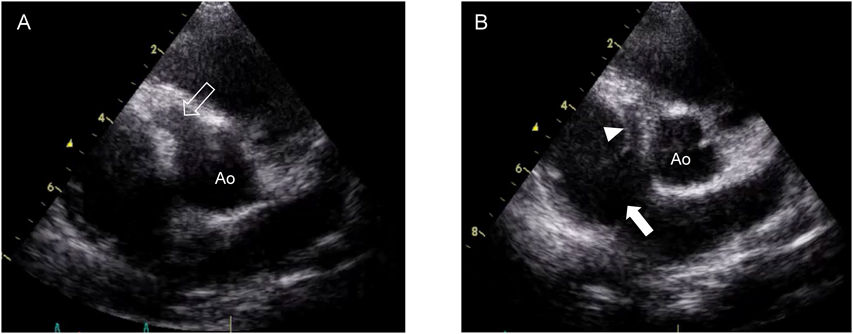

Fig. 2 Aortography frontal view (A) and lateral view (B)

Note that coronary artery fistula (solid arrowhead) arose from enlarged right coronary artery, formed giant aneurysm (solid arrow) at the distal portion, and drained into the right atrium (open arrowhead). Ao, the ascending aorta.